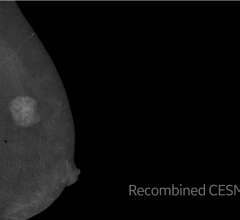

Despite decades of progress in breast imaging, one challenge continues to test even the most skilled radiologists ...